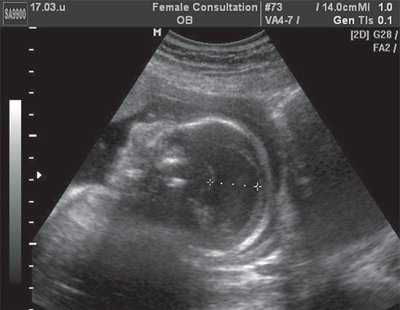

Рис. 5. Эхограмма продольного сечения грудной клетки плода. Стрелкой указан желудок плода, расположенный в его грудной клетке.

Рис. 6. Эхограмма поперечного сечения грудной клетки плода. Стрелкой указан желудок плода, расположенный в его грудной клетке.

Немаловажное значение для оценки лицевых структур плода и четкой идентификации выявленных изменений имело дополнительное использование трехмерной эхографии [3]. Специфические изменения лица плода были заметны "с первого взгляда". При анализе объемных реконструкций была четко видна гипоплазированная нижняя челюсть и близко расположенные глазные яблоки (гипотелоризм) (рис. 7, 8). Аномалий развития других органов не выявлено.

На основании данных эхографического исследования был поставлен диагноз: беременность 22 недели. Множественные пороки развития (сочетание порока Арнольда-Киари II с диафрагмальной грыжей, микрогенией и гипотелоризмом).

При патологоанатомическом исследовании были обнаружены вклинение мозжечка в большое затылочное отверстие, левосторонняя диафрагмальная грыжа, микрогения и гипотелоризм.